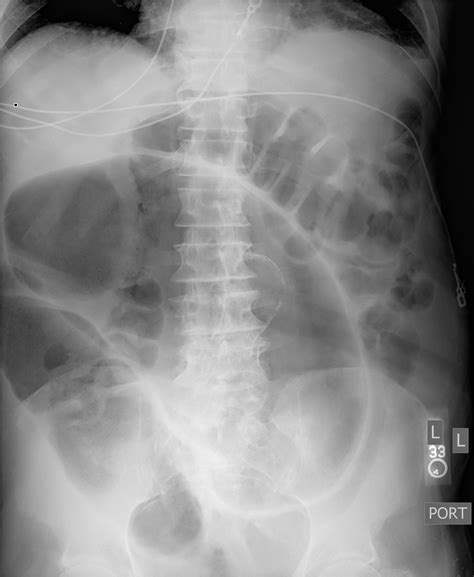

- volvulus coffee bean sign

- coffee bean sign axr

- coffee bean sign meaning

- coffee bean sign radiopaedia